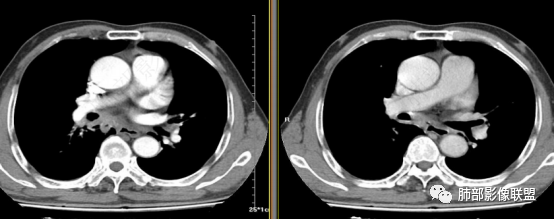

第1个问题:是否是近端支气管堵塞?腔内肿瘤导致远端阻塞性改变?还是外围病灶围绕支气管,引起堵塞?

第2个问题:病灶是否就是内基底段?

第3个问题:支气管堵塞?还是堵塞后还有通畅支气管?

这是支气管,注意看视频支气管连续性的变化。如果上面的支气管完全堵塞,下面的支气管如何解释?

大家考虑这个是支气管腔内占位?引起远端阻塞?还是外围为主病灶侵犯支气管?

南边:个人倾向于外周为主病灶,腔内改变是继发的。原因:病灶围绕支气管,腔内远端无明显阻塞性不张。